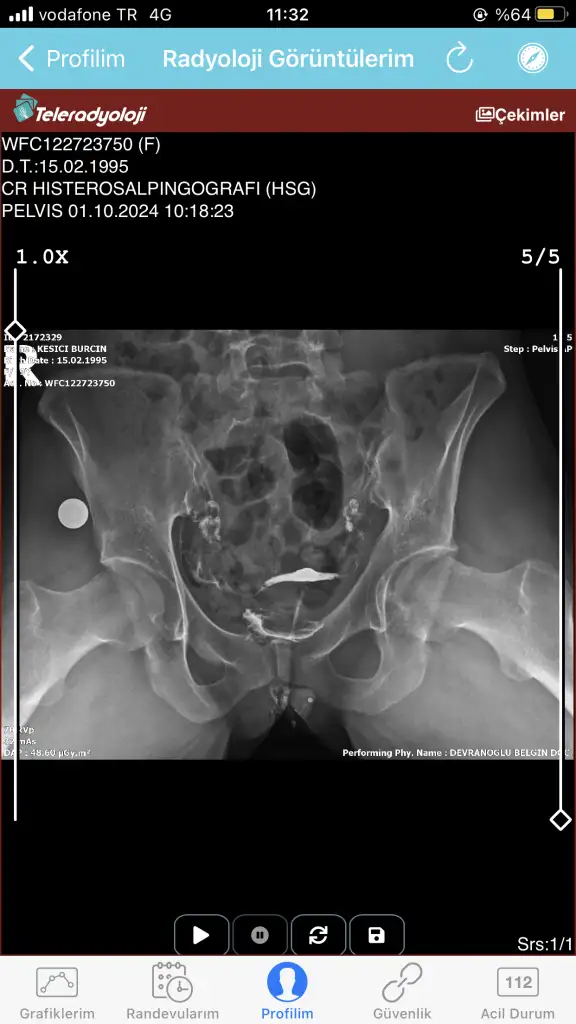

Bugün çekildim doktora gösteremedim daha anlayan yardımcı olabilir mi